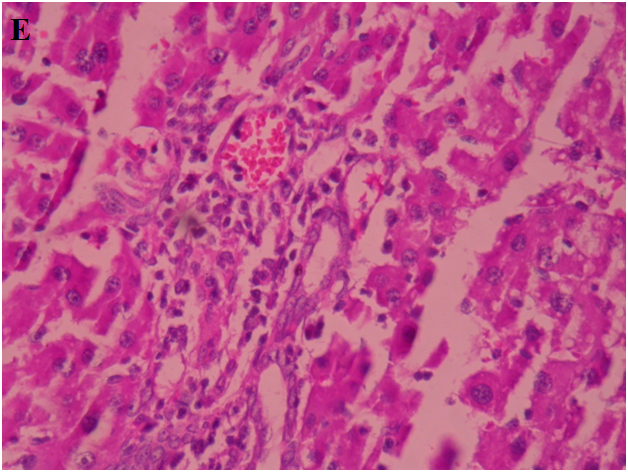

Normal hepatic cell arrangement was observed in the normal liver. Central vein, portal tract, and normal kupffer cells showed no inflammation (fig. 6A). In CCl4 treated group hepatocytes exhibited large degeneration of fatty cells, congestion of central vein and sinusoid, spotty necrosis, focal hemorrhage, ballooning and inflammation of hepatic cells (fig. 6B). In standard silymarin (100 mg/kg) treated group the hepatic globular structure was found to be normal. Mild central vein and sinusoidal congestion were noticed. Regeneration of hepatocytes was also found (fig. 6C). A4EA treated livers (50 mg/kg) exhibited normal rearrangement of hepatocytes surrounding the necrosis and fatty vacuoles (fig. 6D). A4EA treated livers (100 mg/kg) showed mild congestion of central vein and sinusoid. Mild inflammation and focal hemorrhage were seen, whereas no degeneration and ballooning of hepatic cells was observed (fig. 6E). A4nB (50 mg/kg) treated livers showed decreased inflammation of hepatocytes. Mild ballooning and degeneration of injured liver were restored (fig. 6F). A4nB (100 mg/kg) treated livers also showed regeneration of hepatocytes with mild inflammation and ballooning (fig. 6G).

E. A4EA(50 mg/kg)

Fig. 6: Histopathological sections of liver with CCl4 induced hepatotoxicity: A. Normal liver, B. CCl4 induced rat liver, C. Silymarin treated rat liver, D. A4EA (50 mg/kg), E. A4EA(100 mg/kg), F. A4nB(50 mg/kg), G. A4nB (100 mg/kg)

Normal hepatic cell arrangement was seen in the normal liver as compared to CCl4 group as hepatocytes exhibited large degeneration of fatty cells, congestion of central vein and sinusoid, spotty necrosis, focal hemorrhage, ballooning and inflammation of hepatic cells. A4EA (50 mg/kg and 100 mg/kg) showed normal rearrangement of hepatocytes round the necrosis and fatty vacuoles, with mild congestion of central vein and sinusoid. A4nB (50 mg/kg and 100 mg/kg) showed decreased inflammation of hepatocytes. Mild ballooning and degeneration of injured liver were restored. These observations showed that A4EA and A4nB (50 mg/kg and 100 mg/kg) reversed the toxic effects of CCl4 on hepatic architecture.